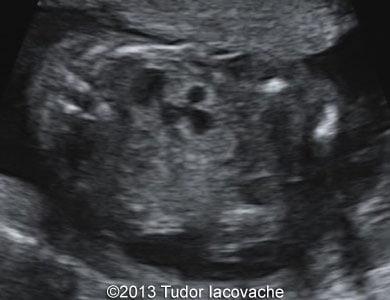

The patient was a 28-year-old primigravida. Fetal hydronephrosis with dilated renal pelvis and calices of the left kidney was noticed at 17 weeks. At 23 weeks the left kidney showed signs of multicystic dysplasia - the enlarged kidney consisted of isolated multiple cysts of various sizes. At 29 weeks the finding was even more striking. The right kidney was normal throughout the pregnancy. The multicystic dysplastic kidney was confirmed after birth.

Images 4, 5 and video 3: 29 weeks of gestation.